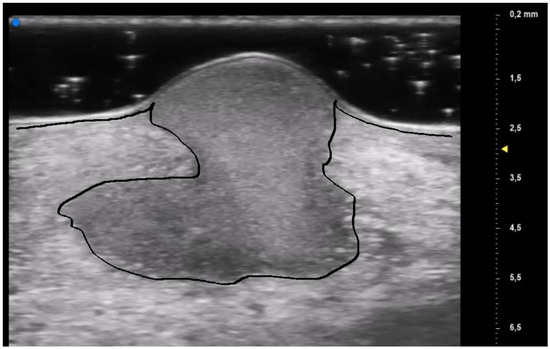

The results obtained by our investigation revealed some UHFUS differences between the inflammatory and non-inflammatory phases. At T0, oval hyperechoic structures, that statistically significantly decreased in T1, were identified in the papillary and reticular dermis (p-value < 0.05) (Figure 4 and Figure 5).

These US findings spared the epidermis and were well demarcated from the surrounding dermis, thus suggesting a hypothesis of “dermal destruction” that we called “tsunami sign” because of the presence of a US image resembling a wave breaking towards the center of the lesion (Figure 6). In T0, hyperechoic oval structures were mainly located at the level of the lesion edges, near V-shaped and U-shaped blood vessels, where the inflammatory response presented a higher activity. Particularly, in T0 an increased expression of U-shaped vessels compared to V-shaped vessels was detectable. In contrast, T1 was characterized by a more uniform vascularization with a significant reduction in U-shaped vessels (p-value < 0.05). These UHFUS findings could be explained by the increased dermal oedema in T0, which resulted in surrounding connective tissue compression and morphological blood vessels changes.

Figure 6. Early PG lesion: the purulent material (included by the black line) is well demarcated and undermined from the surrounding dermis giving a wave-like appearance, the so-called “tsunami sign”.